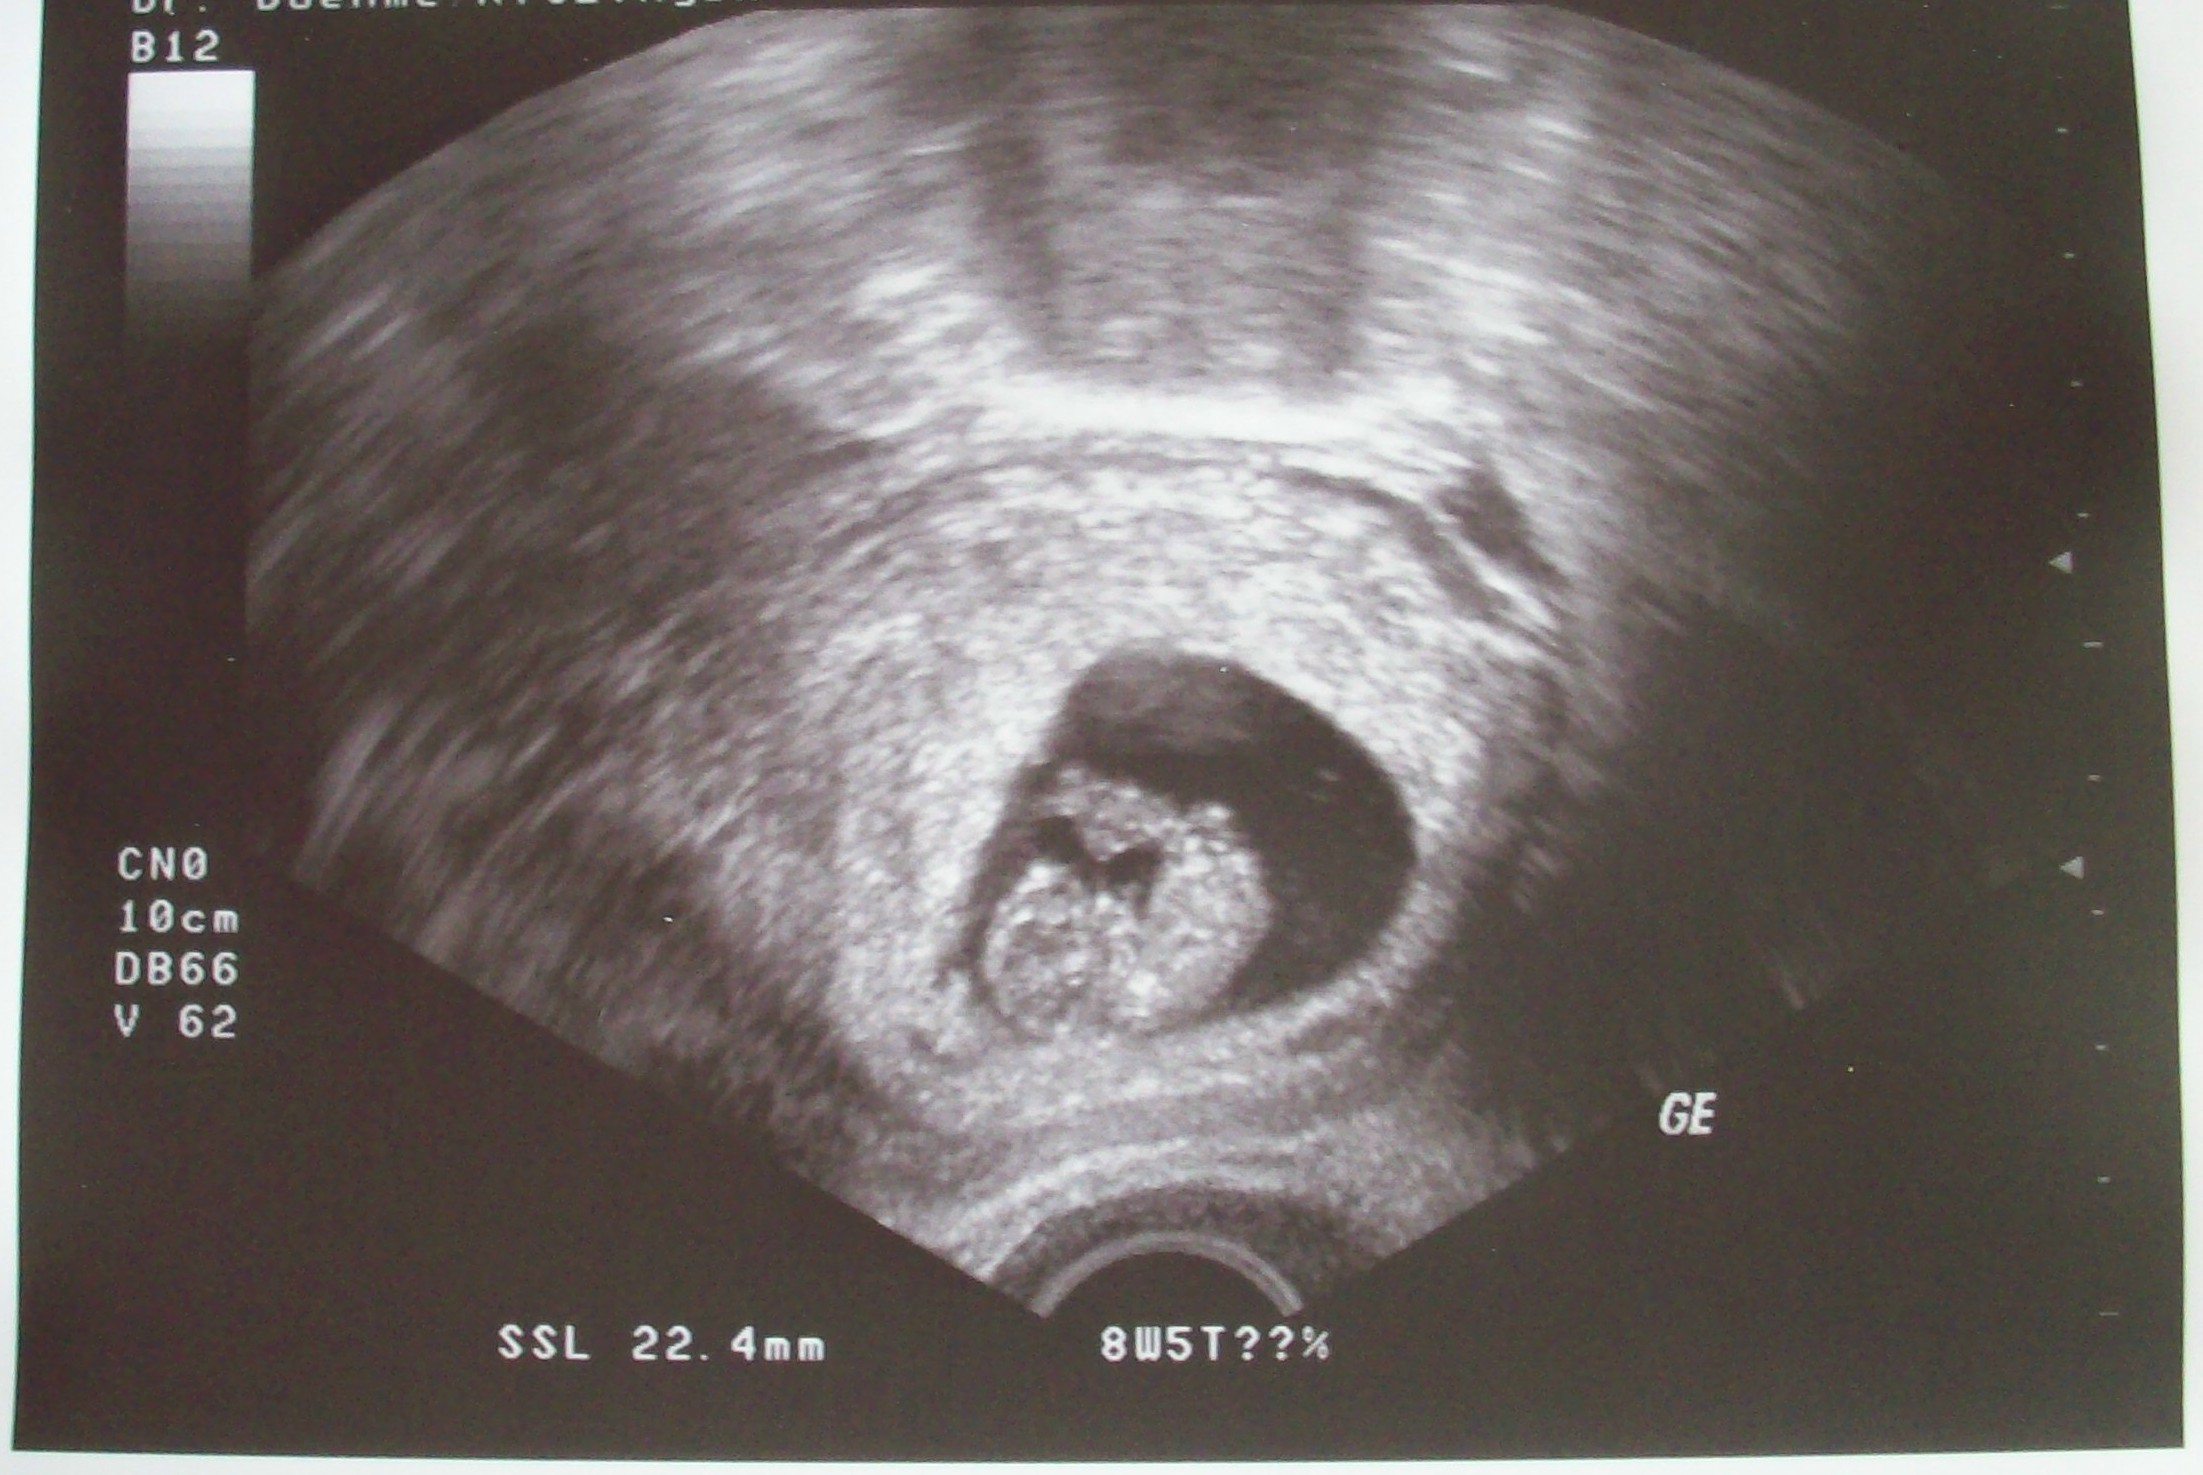

na ausgeschlafen? Bin zurück vom Gyn. alles ok. Ü-Stim. hält sich in Grenzen, Aszites hab ich garnix mehr, (ähm Bauchwasser), d.h. habe heute ein mal HCG i.m. bekommen zur Unterstützung für meine Krümelchen, jetzt weiß ich auch wieso ich nicht solange auf den SS-Test warten muß, hab mal nachgefragt. Also habe heute Blutentnahme gehabt, vor der HCG-Spritze quassi als nullwert, hab am Mittwoch nochmal Blutentnahme und am Freitag dadurch bekommen die Vergleichswerte, weil jeder HCG unterschiedlich abbaut, will heissen ausgehend von Mittwoch auf Freitag jenachdem ob Wert gleichbleibt oder steigt sind Krümelchen da die Fleissig HCG produzieren.